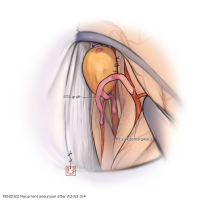

術後イラストシリーズ

監修:太田 仲郎